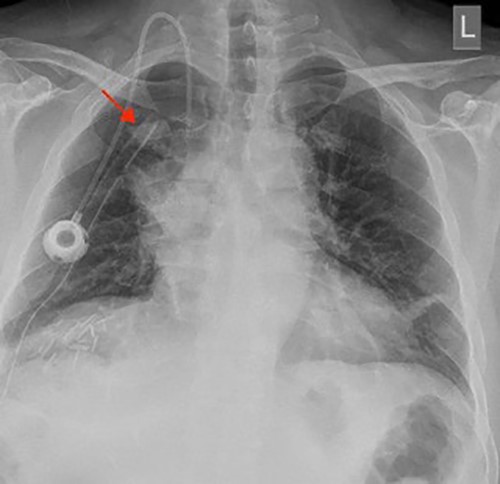

A chest X-ray at the time of admission showed right upper lobe mass (Fig. 1). Tru-Cut biopsy was performed and confirmed the diagnosis of non-small cell carcinoma (Figs 2 and 3). Multiple sections showed two nodules composed of well differentiated adenocarcinoma. The largest one measuring 4 mm from the resection margin, 2.5-cm away from hilar region and 5 mm from the outer surface. Smallest nodule was also composed of well-differentiated adenocarcinoma present 3 mm from the outer surface.

Chest X-ray (PA view) showing the right upper lobe mass. PA: posterior anterior.